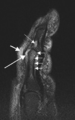

Magnetic resonance images of sacroiliac joints. Shown are T1-weighted semi-coronal magnetic resonance images through the sacroiliac joints (a) before and (b) after intravenous contrast injection. Enhancement is seen at the right sacroiliac joint (arrow, left side of the image), indicating active sacroiliitis.